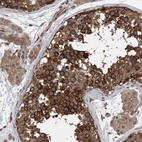

Immunohistochemical staining of human cerebral cortex shows strong cytoplasmic positivity in neurons.